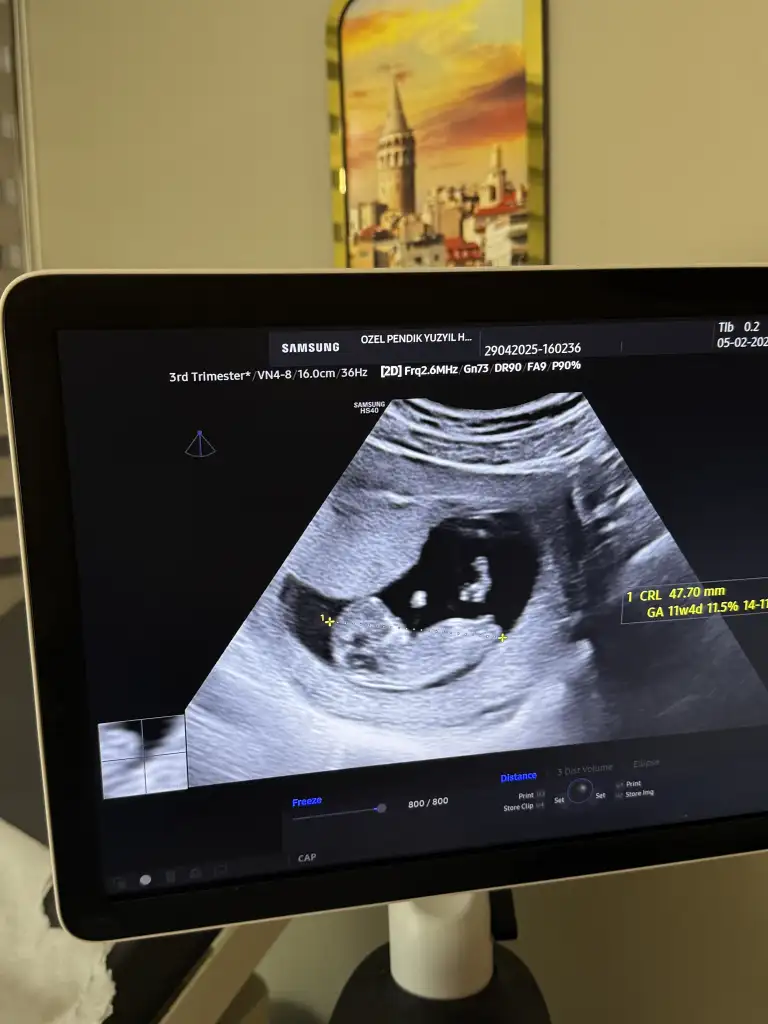

bana da bakabilir misinizNe kadar net görüntüler almış doktor. Şu an çok küçük iki bacak arası boş görünüyor ama bu hafta kız erkek görünüşü benzer oluyor zaten 1/2 hafta daha bekleyin netleşir

bana da bakabilir misinizHayırlısı olsun kız gibi sanki kese yuvarlak

Bence kızEki Görüntüle 3585691 benim içinde tahminde bulunur musunuz![]()

maşallah acaba kaç günde çıktı fetal dna sonucunuz bende cuma verdim bekliyorum genoks firması. sizinle çok benziyoruz bana da dün 11+4 kız mı sanki dedi sonra bir çıkıntı var erkekte olabilir net değil dedi :)oğlum oluyo benim cinsiyetimiz belli oldu

bende hiç çıkıntı gözükmedi 11+4te gittiğimde bacak arası boş ama bu görüntü bizi yanıltabilir erken cinsiyet için dedi . dediği gibi de oldu :) haftasonunu saymazsak 5 günde çıktı.maşallah acaba kaç günde çıktı fetal dna sonucunuz bende cuma verdim bekliyorum genoks firması. sizinle çok benziyoruz bana da dün 11+4 kız mı sanki dedi sonra bir çıkıntı var erkekte olabilir net değil dedi :)

Tahmin yapabilirmisiniz 13+1Erkek olduğunda net bir şekilde bir çıkıntı görünüyor